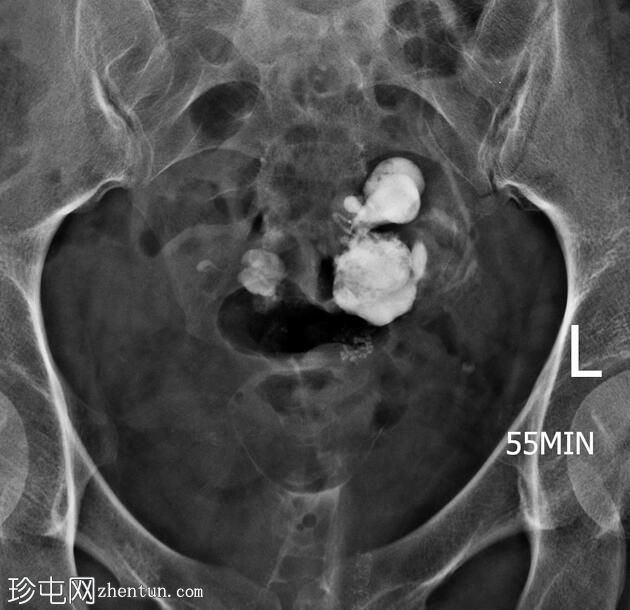

子宫位于盆腔正中线,形态及轮廓正常。

宫颈管长度及黏膜表面正常,扩张正常。

左侧输卵管充盈,管腔扩张,造影剂残留,无因输卵管积水导致的溢液。

右侧输卵管峡部造影剂显影中断,造影剂远端呈球状扩张。

输卵管积水是指输卵管内充满液体的扩张。